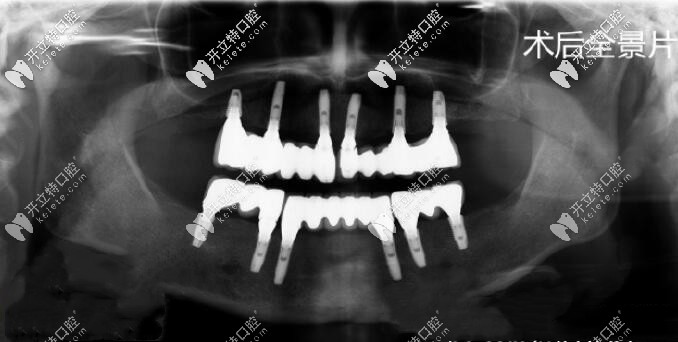

種植過程示意圖